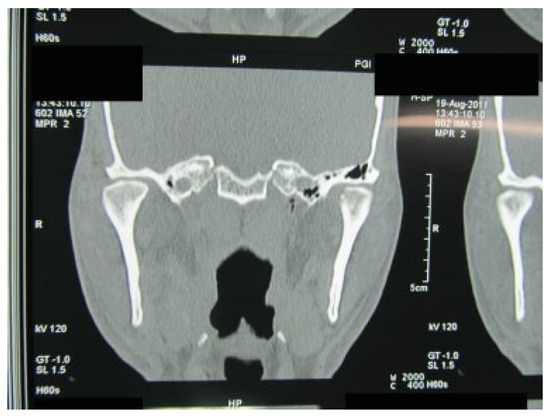

Superolateral Dislocation of Bilateral Intact Condyles—An Unusual Presentation: Report of a Case and Review of Literature

:1. Case Report